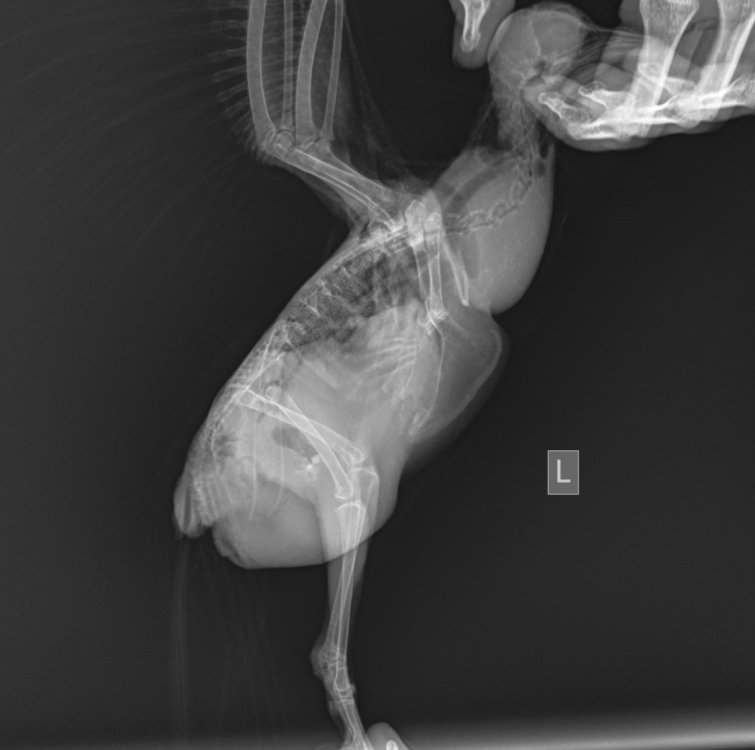

Здравствуйте. Птице по словам  удалённого врача надо отвести жидкость из брюшной полости. Дышит тяжело, на лапы уже не становится. Очный приём только завтра в час дня в другом городе. В Ростове на Дону сделать это некому. Единственный врач который принимал меня на больничном с травмой руки. Есть шанс вывести таблетками все-таки ? Может можно в дом условиях отвести?

иду в аптеку за мочегонным могу видео чуть позже дать ссылку. Но там сто процентов асцит, по рентгену похоже, визуально тоже похоже и со вчерашнего дня объём увеличился.

@маленький принц съездили вчера, откачали жидкость. Сдали помет и мазок из зоба бакпосев, и пцр на сальмонеллез, хламидиоз, микобактерии и ещё какой-то, забыла. Будем выяснять причину асцита. Из слов врача поняла, что прогноз осторожный. Из-за затруднённого дыхания в следствие асцита пошли изменения в сердечке и с лёгкими не очень, воспаление. Но я смотрю на Чижика и не вижу, что он помирать собрался, после того как жидкость откачали проснулся зверский аппетит и повысилась активность. Буду надеяться, что выживет.

Асцит возможен ещё из-за нарушений в работе печени сказал врач, а у Чижика проблемы с печенью есть. Увеличена и помет был желтый.

рентген делали когда был асцит, сейчас его нет.

Рентген и анализы от 29 августа